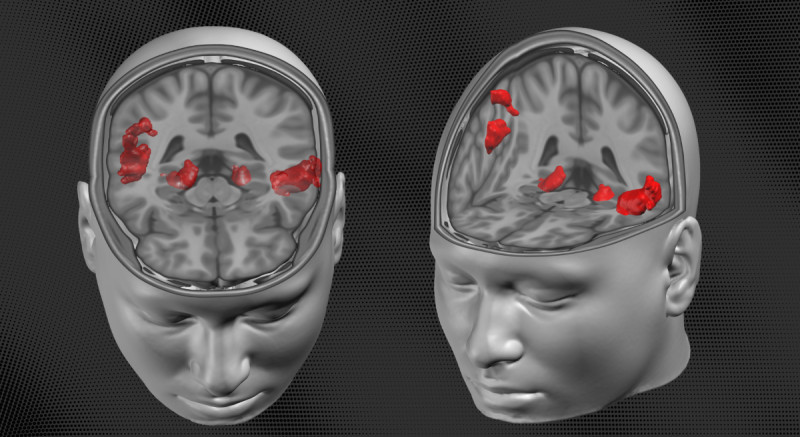

Nová studie vědců z CEITEC Masarykovy univerzity odhalila, že válečný stres má dlouhodobý dopad na strukturu mozku lidí přímo zasažených konfliktem, přičemž ti, kteří konflikt nezažili, nemají strukturální změny, ale vykazují posttraumatický růst, což naznačuje, že válečné zkušenosti rodičů se mohou přenášet na jejich potomky skrze výchovu a životní prostředí. #válečnýstres #duševnízdraví #výzkummozku

Mozek si válku pamatuje i po desítkách let